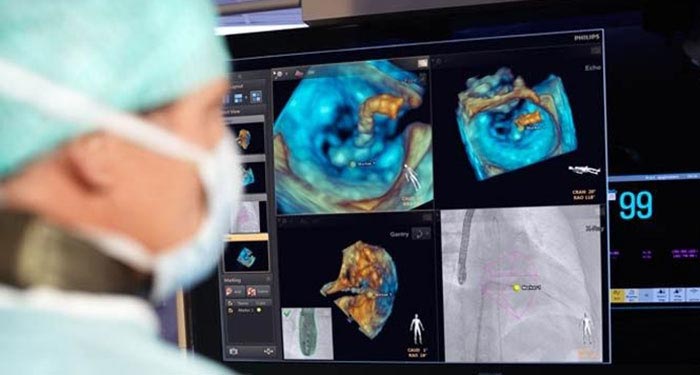

Azurion’ s next leap in lab integration and 3D imaging gives you control over an array of compatible applications from a single touch screen interface at table side. Extend the life of your interventional lab with a SmartPath catalyst conversion or enable advanced and complex procedures in the fields of interventional radiology, cardiology, neuroradiology, oncology and surgery.

Our imaging technology ClarityIQ, combines advanced, real-time image noise reduction algorithms with state-of-the-art hardware. Together, they form a flexible digital imaging pipeline designed to perform individual image processing algorithms more efficiently. This unlocks superb visualization and significant dose reduction capabilities for healthcare facilities. ClarityIQ is available as an option on Azurion systems.

Today, the Philips portfolio of image-guided therapy (IGT) solutions uniquely integrates best in class imaging systems and software, with specialized diagnostic and therapeutic devices to support exceptional treatment for even the most complex procedures.